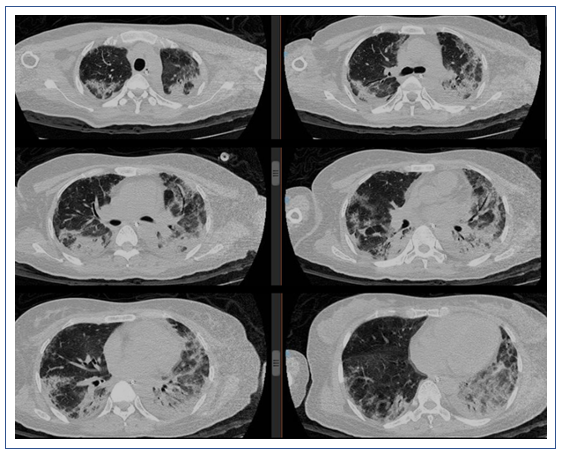

复查X线胸片:双肺多发渗出进展,左肺大片实变(图6)。

2019年1月16日复查胸部CT:双侧中下肺实变影较1月9日增多(图7)。

图7 患者复查胸部CT与前对比

左:2019年1月16日CT;右:2019年1月9日CT

2019年1月25日,患者胸部CT显示双下肺实变较前有所吸收(图11)。

图11 2019年1月25日患者胸部CT

2019年2月1日患者胸部CT显示,上肺渗出进展(图14)。

2019年2月25日患者胸部CT示双肺病变较前吸收(图16)。

图17 2019年3月11日患者胸部CT